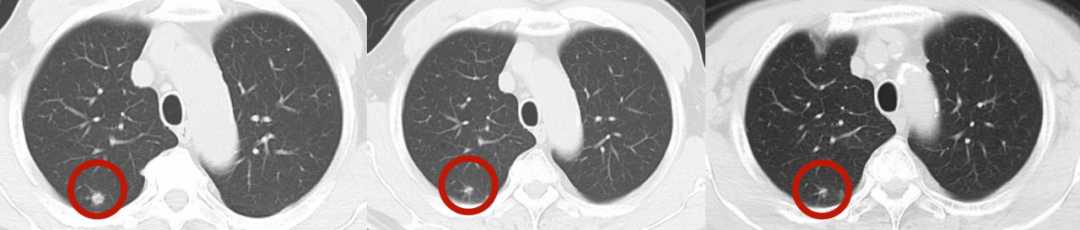

整个治疗过程无创、无痛,患者全程耐受良好,无明显不适症状。治疗结束后1个月、2个月的随访检查显示,患者肺部肿瘤较治疗前明显缩小,各项身体指标稳定,治疗效果完全达到预期,成功实现了 “精准杀伤肿瘤、最大程度保护正常组织” 的治疗目标。

(左图为放疗前病灶影像,中图为放疗后1月病灶影像,右图为放疗后2月病灶影像,可见肿瘤逐步缩小)